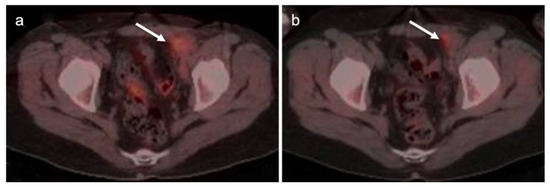

2.6. Vulvar Carcinoma